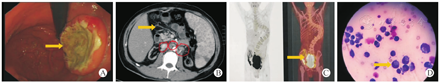

肾移植术后PTLD的临床诊断是结合临床表现、实验室检查、体征、影像学检查等,组织病理学检查是确诊的金标准。确诊PTLD的依据包括:(1)受者出现如发热、盗汗、体重下降、淋巴结肿大、原因不明肿块等症状和体征,累及移植肾可出现移植肾功能不全。(2)实验室检查血液中不断增加的EB病毒载量,病毒衣壳抗原(VCA) IgA抗体、EB病毒VCA-IgM抗体阳性。或者活检标本检测到编码RNA原位杂交EBER1染色阳性。(3)B型超声、CT、正电子发射计算机断层显像(PET-CT)检查发现中枢神经系统、实体器官、胃肠道及腹腔等部位的肿块。(4)经内镜、淋巴结活组织病理学检查提示有明显的PTLD表现(图1)。

13例确诊受者病变位置分布在肺部1例,胃肠道8例,区域淋巴结2例,皮肤1例,颅内1例,首发无明显特征,体检发现3例,腹部症状起病(腹胀、上腹部不适、腹痛、消化道出血)8例,发现局部肿块2例。Ann Arbor分期IEA1例、 IIB1例、IIEA5例、IIEB3例、IVEA1例、IVB2例,IPI评分2分2例,3分8例,4分3例。均由组织病理学检查确诊,经多学科联合会诊后如需手术治疗转至各个专科继续治疗,如无须手术治疗则转至血液内科进行化学药物治疗。